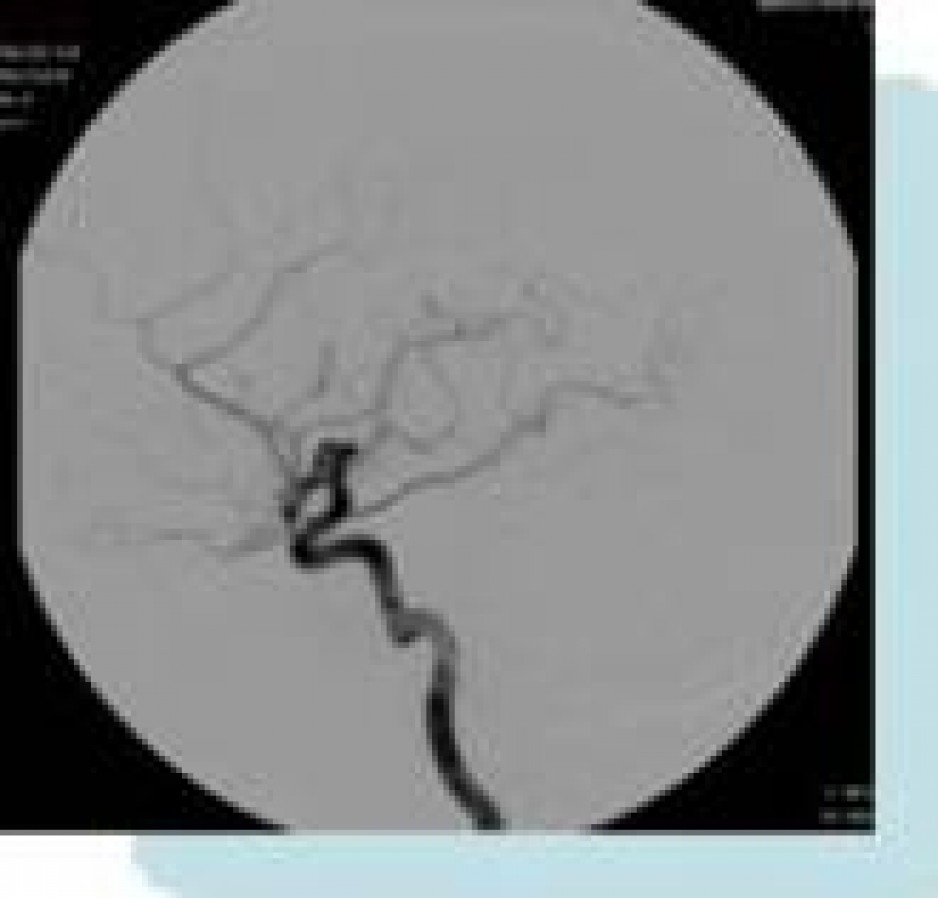

internentional radiology image

"Special Procedures" or "Interventional Radiology" is a growing subspecialty in which both vascular and nonvascular diseases are diagnosed and treated. It is a minimally invasive technique utilizing small catheters and catheter-based instruments. These procedures are performed with local or intravenous sedation and are guided by radiological imaging such as fluoroscopy,  CT or ultrasound.